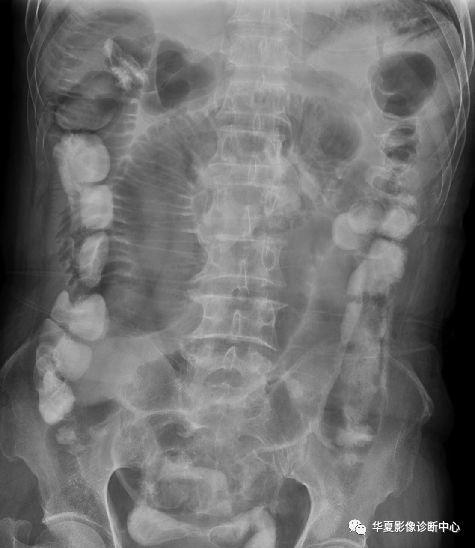

结肠梗阻结肠肠管扩张明显,升,降结肠区肠管内可见多个气液平面.